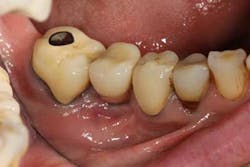

A 52-year-old woman with a noncontributory medical history, taking no medications with no reported food or drug allergies, was referred to my office from a general dentist in order to obtain a second opinion. She had a lower right premolar implant placed in an oral surgery office five years ago that was suffering from severe peri-implantitis. (Fig. 1) Her first dentist told her that the implant had to be removed and that her treatment options were a fixed partial denture in the form of a three-unit bridge or a partial denture because re-implantation was not feasible. In addition, he sent her to a periodontal office that verified his statement, telling the patient that because of nerve proximity and the poor chance of ridge augmentation, re-implantation was unlikely. When she asked if saving the implant was possible, both the dentist and the periodontist told the patient that because of the level of bone loss, regenerative treatment would not work.Fig. 4

Fig. 5